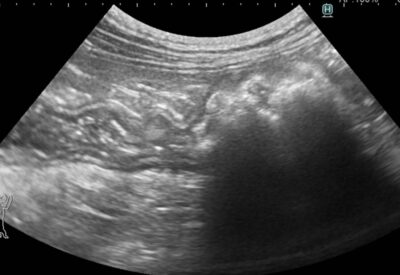

胆嚢破裂

犬

胃のできもの/嘔吐・吐出

腫瘍科(ガン)/外科

犬の胃腺癌